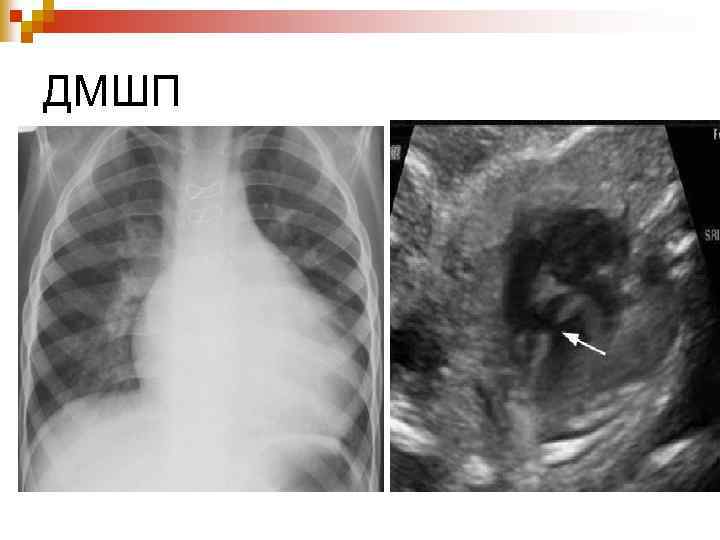

Діагностика ЕКГ: ознаки гіпертрофії ЛШ або обох шлуночків, при склеротичній формі гіпертензії – тільки правого; n Ехо-КГ: візуалізація самого дефекту; n Рентгенологічно: Ш посилення та повнокрів’я легеневого малюнку, розширення коренів легень, збільшення розмірів серця; Ш У період декомпенсації: збіднення легеневого малюнку. n

ДМШП

Диагностика При рентгенологическом исследовании органов грудной клетки описывают форму сердца и состояние легочного рисунка, определяют размер кардиоторакального индекса (КТИ). Все эти показатели имеют свои особенности при разных степенях лёгочной гипертензии. В первой, гиперволемической стадии, выявляется сглаженность талии и погруженность верхушки сердца в диафрагму, увеличение КТИ. Со стороны легочного рисунка отмечается его усиление, нечеткость, размытость. Крайней степенью гиперволемии в лёгких является отёк лёгких. В переходной стадии лёгочной гипертензии отмечается нормализация лёгочного рисунка, некоторая стабилизация размеров КТИ. Для склеротической стадии лёгочной гипертензии характерно значительное увеличение размеров сердца, причем в основном за счёт правых отделов, увеличение правого предсердия (формирование прямого атрио-вазального угла), выбухание дуги лёгочной артерии (индекс Мура более 50%), приподнятость верхушки сердца, которая образует с диафрагмой острый угол. Со стороны лёгочного рисунка часто описывается симптом «обрубленного дерева» : яркие, чёткие, увеличенные корни, на фоне которых лёгочный рисунок прослеживается только до определённого уровня. На периферии имеет место признаки эмфиземы. Грудная клетка имеет вздутую форму, ход ребер горизонтальный, диафрагма уплощена, стоит низко.